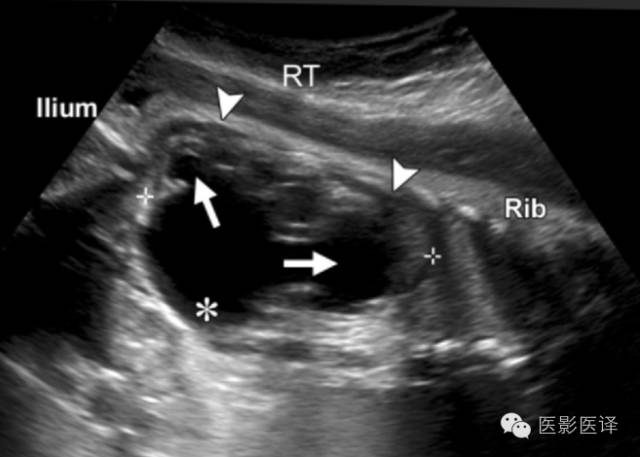

胎儿肾盂积水,可清晰看到肾盏与肾盂相通(图10)。周围肾实质可能回声正常、变薄、回声增强或者发展为阻塞性囊性发育不良。肾盂积水的位置邻近于脊柱,这有助于与其他腹部肿块如卵巢囊肿进行鉴别。大多数胎儿肾盂积水是轻度的,Sairam等将肾盂前后径4-7mm定义为轻度积水。大多数病例会在产前及产后自发地好转,极少数病例需要外科干预。然而,诸多产后疾病的发生风险,包括肾盂输尿管交界处阻塞、输尿管阻塞、梨状腹综合征、VATER综合征(脊椎缺陷、肛门闭锁,合并食管闭锁的气管食管瘘,肾和桡骨异常),孤立肾、肾肿瘤等,会随着肾盂积水严重程度的增加而增加。

图10.肾盂积水。胎儿的纵向超声图像显示显著的肾盂积水,积水继发于肾盂输尿管交界处梗阻。注意那些与肾盂(*)相通的扩张的肾盏(箭)。肾实质的厚度(箭头)比卵巢囊肿壁厚的多。RT=右侧